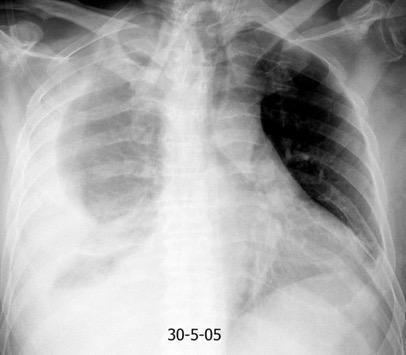

Marzo 2014: Perforación longitudinal distal secundaria a episodio de vómito (síndrome de Boerhaave). Derrame pleural izdo. que evoluciona a empiema.